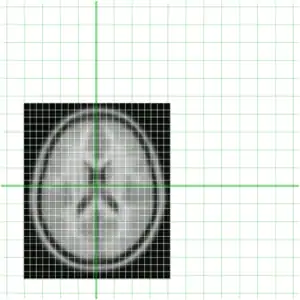

Of course being a MINC file, both of these files represent a sampling of a world space (as defined by starts, steps and direction cosines -- use mincinfo to see this). In order to get an understanding of this, our two files are shown again below with their relative position in world space shown in green.